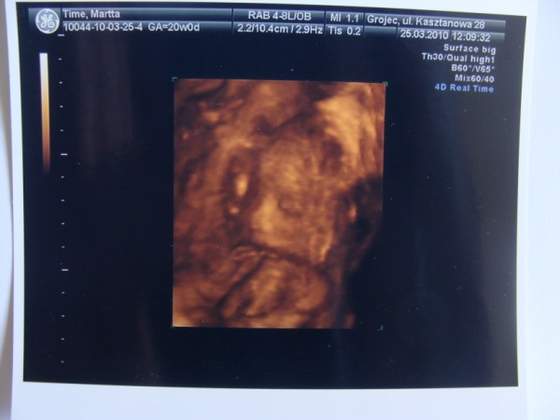

Niestety nadal nie znam płci... Przykleił się do macicy i za nic nie chciał się pokazać, tylko kolanko co najwyżej i to dopiero pod koniec USG. Mam filmik ale coś mi się dzieje z internetem i nim wgram na youtube, to przerywa i taki finał. Zdjęcie mi dał tylko jedno, jestem w szoku z tą kością nosową

A tu jeszcze dodaję zdjęcie opisu ciąży, możecie mi powiedzieć, czy to normalne, że te różne parametry są na różnym etapie rozwoju? Wy jesteście w tym bardziej oczytane, więc ufam